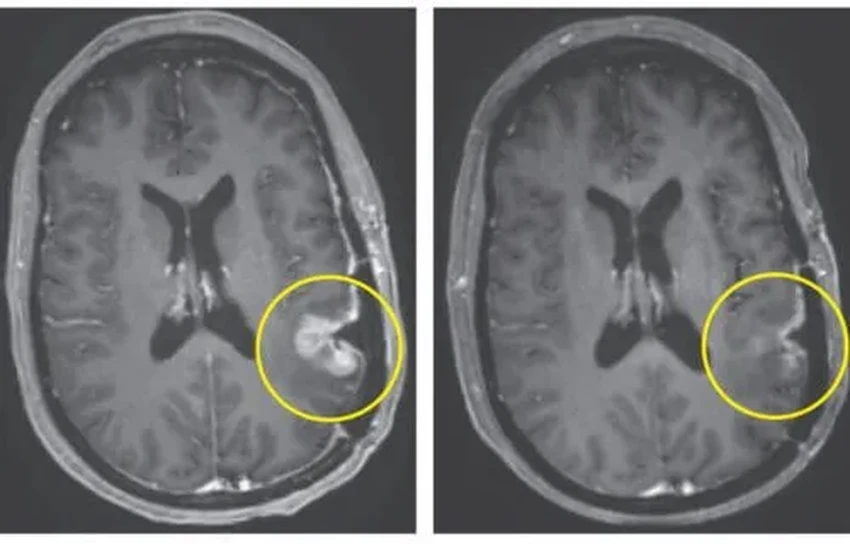

Всего через несколько дней после одной-единственной инфузии опухоли стали стремительно сокращаться. И один из случаев просто ошеломил: почти полное исчезновение опухоли за пять дней. Пять дней! Мы привыкли, что борьба с раком измеряется месяцами и годами, а тут — меньше недели на драматический ответ. Заставляет задуматься, на что еще способна наша иммунная система, если дать ей правильные инструменты?

Конкретные цифры: у 72-летнего пациента опухоль уменьшилась более чем на 60%, и этот эффект держался полгода. А 57-летняя женщина увидела на снимках почти полную регрессию своей опухоли уже через 120 часов после укола. Это не просто «многообещающие результаты» — это взрывная волна в онкологии.